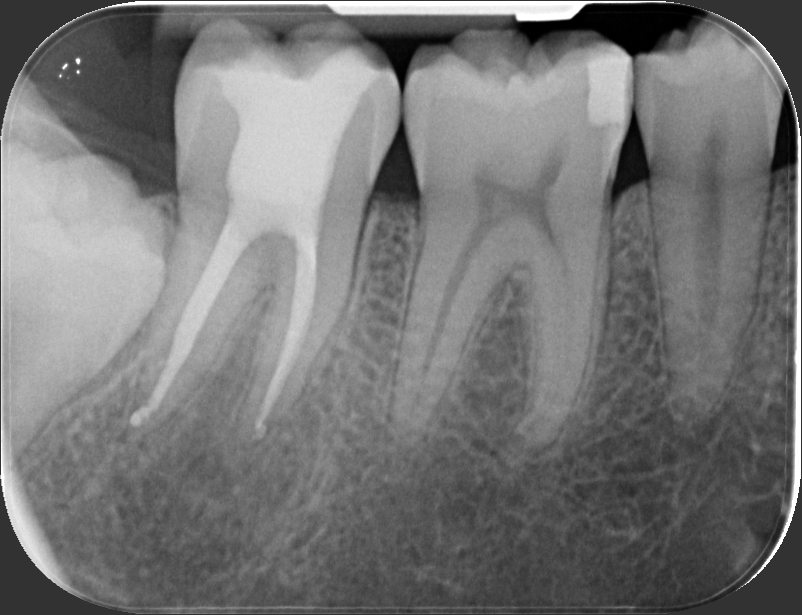

ENDODONZIA

Caso clinico – ritrattamento ortogrado di 1° molare inferiore con lesione

Caso clinico – trattamento ortogrado di 2° molare inferiore